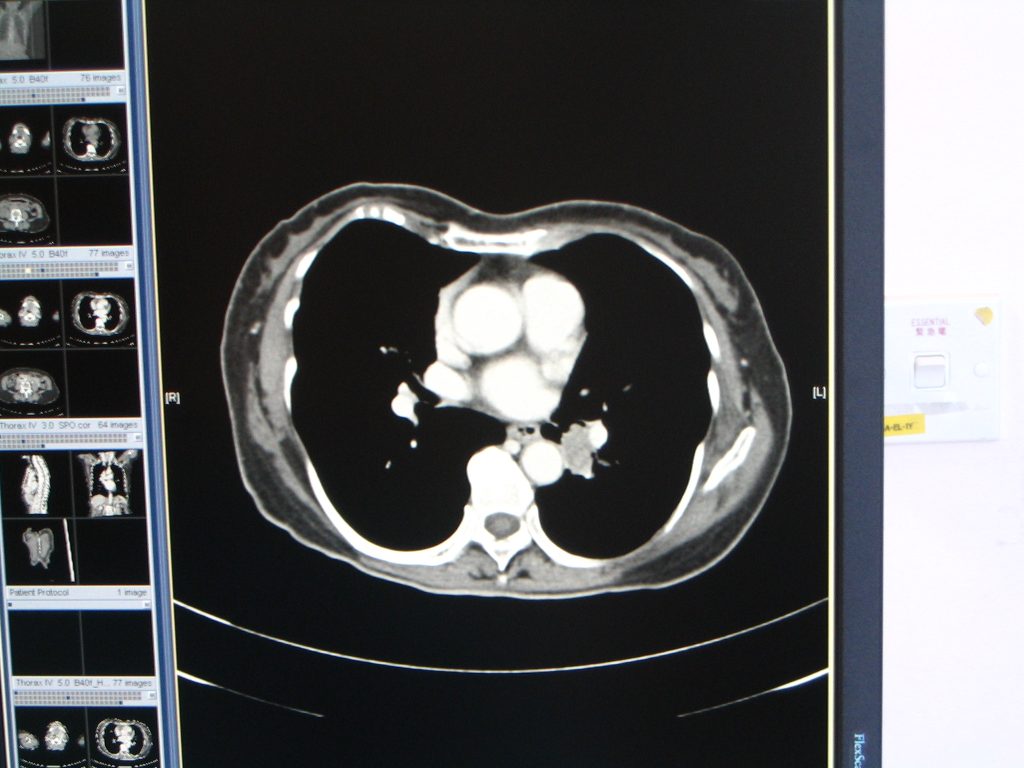

Computerized tomogram of thorax on 6 April 2010 for KH showed an enhancing lesion at left infrahilar region measuring 1.5 x 2.3 x 2.5cm in LLL with erosion into LLL bronchus. (fig. 2)

Fig.2 (Above) Patient 1: Computerized tomogram of thorax on 6 April 2010 showed an enhancing lesion at left infrahilar region measuring 1.5 x 2.3 x 2.5 cm in LLL with erosion into LLL bronchus.